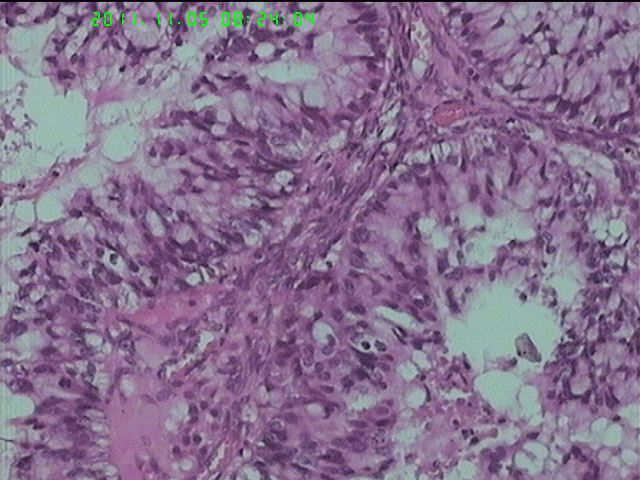

37岁女性患者,左卵巢肿块术中快速:恶性。术后左卵巢囊实性肿块14*9*5CM,灰黄色,部分乳头状,粘液样外观;子宫内膜厚1.5CM;网膜见多个小结节。图1--14左卵巢  15-19网膜  20--23宫腔

左卵巢黏液性腺癌伴内膜网膜转移.

粘液腺癌(部分呈低分化)

卵巢粘液性囊腺癌伴内膜及网膜转移。

图1、4、5、6、11中可见疏松组织,网状结构,并见可疑透明小体,加上患者年纪较年轻,卵黄囊瘤不能除外,粘液腺结构可能是卵黄囊中的内胚层成分。且形态上与网膜结节相似。